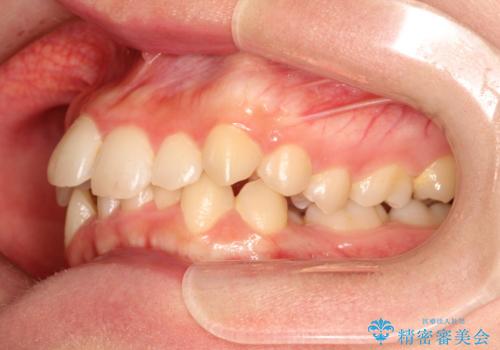

全体的ながたつき ワイヤーによる抜歯矯正で整った歯並びへ

- 上下の全体的ながたつきが気になるとのことで来院されました。

上下左右の前から4番目の歯を抜歯をして、ワイヤー矯正にて並べる計画としました。

患者様が装置を早期に除去したいという希望もあり、少々下の前歯のがたつきが残った状態で矯正を終了しました。

全体的ながたつきがなくなり、見た目の印象がよくなりました。